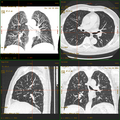

Kombination aus multiplanarer Reformatierung und sliding thin slab. Der Bildkursor befindet sich im rechten Lungenflügel. Die sts-Bildstapel werden in Form von MIP-Darstellungen gezeigt (STS-MIP).[52] Links oben befindet sich eine VR-Darstellung der Lunge; sie zeigt einen Blick auf die koronal an Kursorposition geschnittene Lunge. -